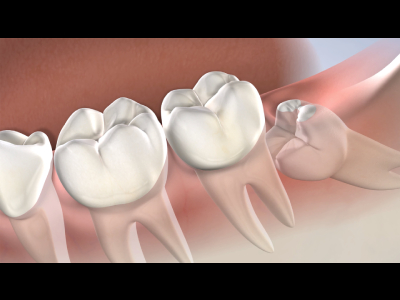

experienced dentist, he specializes in procedures such as Root Canal Treatment, Dental

Extractions, Dental Implants, Crowns, Full Mouth Rehabilitation, and Clear Aligners